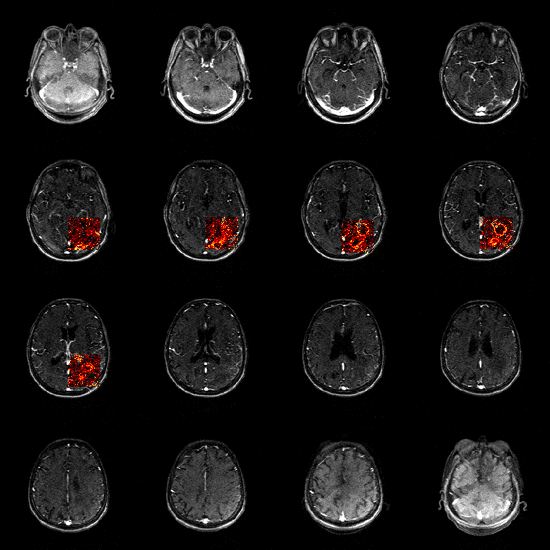

Software for Magnetic Resonance Imaging

Software for Analysing Data from Dynamic Contrast-Enhanced Magnetic Resonance Imaging (DCE-MRI), Cardiac Magnetic Resonance (CMR) …